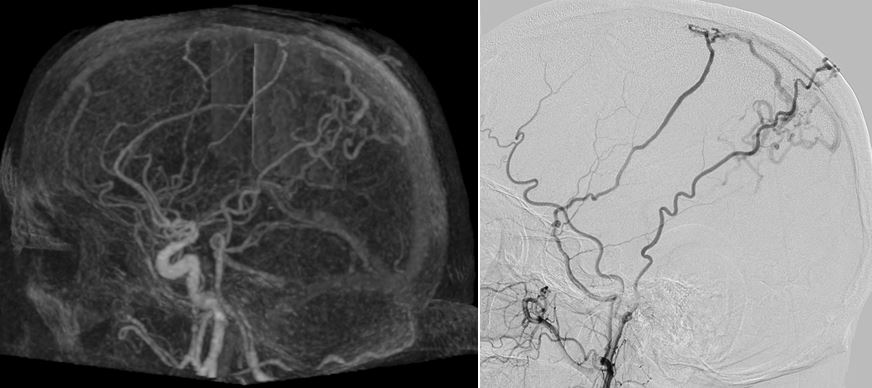

This prospective study compared 4D-CTA and DSA for the detection or arterio-venous shunts and found that CTA was able to replace DSA as the first work-up modality.

Article: High sensitivity and specificity of 4D-CTA in the detection of cranial arteriovenous shunts